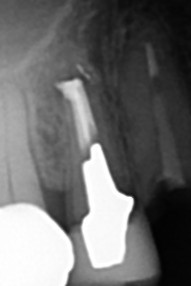

【右上4番根尖外に不透過像が出ている】

【赤矢印 赤矢印の先にも小さな不透過像が確認できる】

【予想通り根管外の異物除去は困難】

【術中根充を行う】